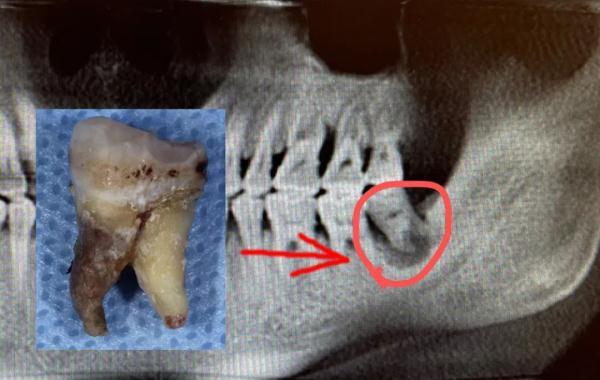

陳申國說,這么嚴重的感染,一般要兩個星期才能恢復,蔣先生的身體確實好,才一個多星期,病灶處的膿液已經(jīng)排得差不多了,可以拔除那顆病牙了。

問題牙齒